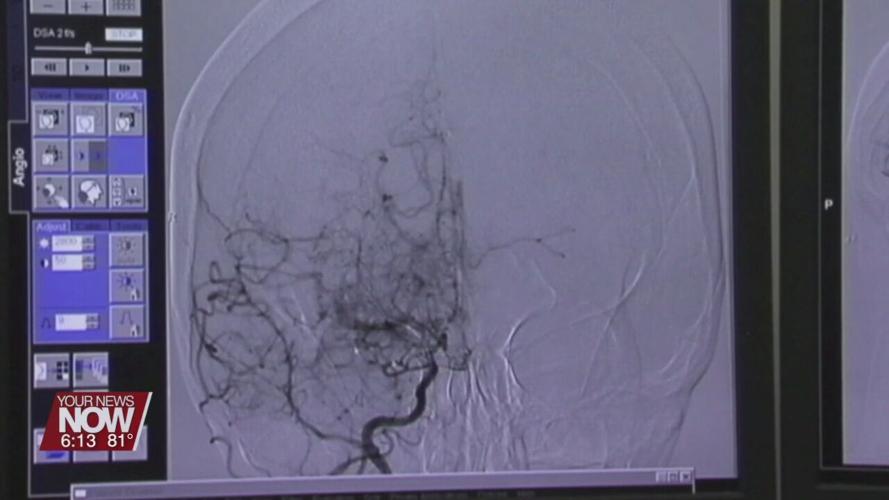

“If somebody gets to the hospital between 3 and 4 ½ hours of having a stroke we can give TPA, Tissue Plasminogen Activator, which is a clot-buster and can dissolve that clot so the blood flows back to that part of the brain and people do better,” adds Riess. “If there is a large artery that is blocked. We can even have an endovascular procedure. Where a procedure or a catheter is fed through the arteries and the clot can be removed and people do better after that.”